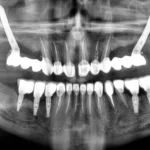

Bardzo wielu pacjentów ma mylne wyobrażenie o strukturze implantu. Warto wiedzieć, że jest on niedostrzegalny. Pełni rolę sztucznego korzenia, który zostaje wszczepiony w szczękę pacjenta i to właśnie na nim mocuje się koronę, czyli widoczną część zęba. Implanty zębowe wykonuje się z tytanu, nieco rzadziej z cyrkonu (wtedy mówimy o implantach ceramicznych). Po wszczepieniu ich w kości szczęki, nie od razu mocowana jest na nich korona, najpierw pacjent musi przejść przez proces integracji wszczepu z tkankami w jamie ustnej. Aby uzupełnienie było estetyczne, wstawiona zostaje tymczasowa korona, która jedynie imituje wygląd naturalnego zęba. Proces rekonwalescencji zamyka się zwykle w czterech-sześciu miesiącach i dopiero po tym czasie można w pełni skorzystać z rozwiązań, oferowanych przez implanty.

Braki w uzębieniu mogą zostać uzupełnione na kilka różnych sposobów. Najpopularniejszym rozwiązaniem są klasyczne protezy, jednak często wiążą się z dużym dyskomfortem. Wielu pacjentów odczuwa strach, że proteza wypadnie w najmniej spodziewanym momencie. Drugą możliwością, zdecydowanie bardziej stabilną, są mosty. Niestety ich założenie wymaga opracowania sąsiadujących z nim zębów, a ponadto nie sprawdzą się w przypadku dużych braków. Na dzień dzisiejszy najbardziej kompleksowym rozwiązaniem jest wszczepienie implantów. Są przeciwieństwem protez, bo gwarantują najwyższa możliwą stabilność z wszystkich uzupełnień. Ich zastosowanie nie wiąże się z koniecznością naruszenia zdrowych zębów, a implanty mogą z powodzeniem zastąpić nawet wszystkie zęby.